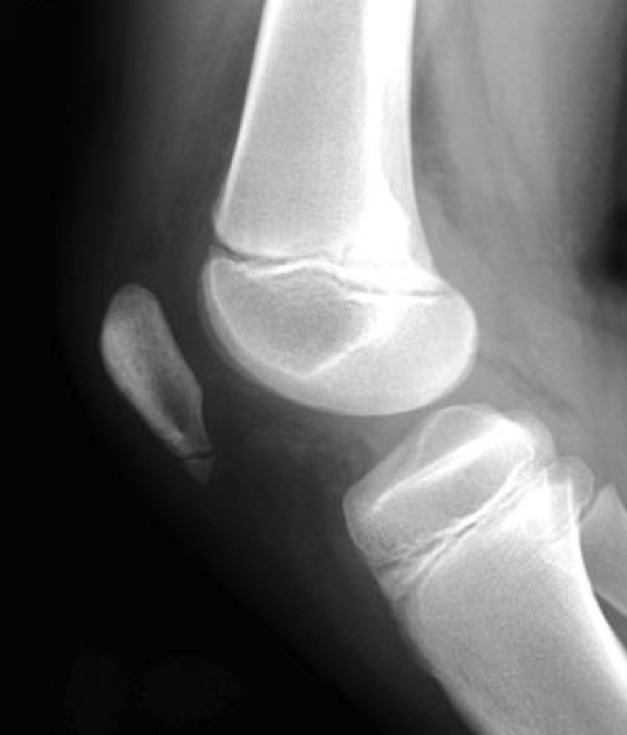

Sinding 2

In